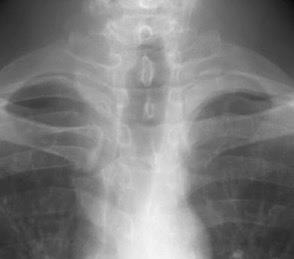

Viejo delgado

Se forma con las inserciones claviculares de ambos músculos esternocleidomastoideos. Particularmente vista en emaciados, personas muy delgadas y laringuectomizados previamente.